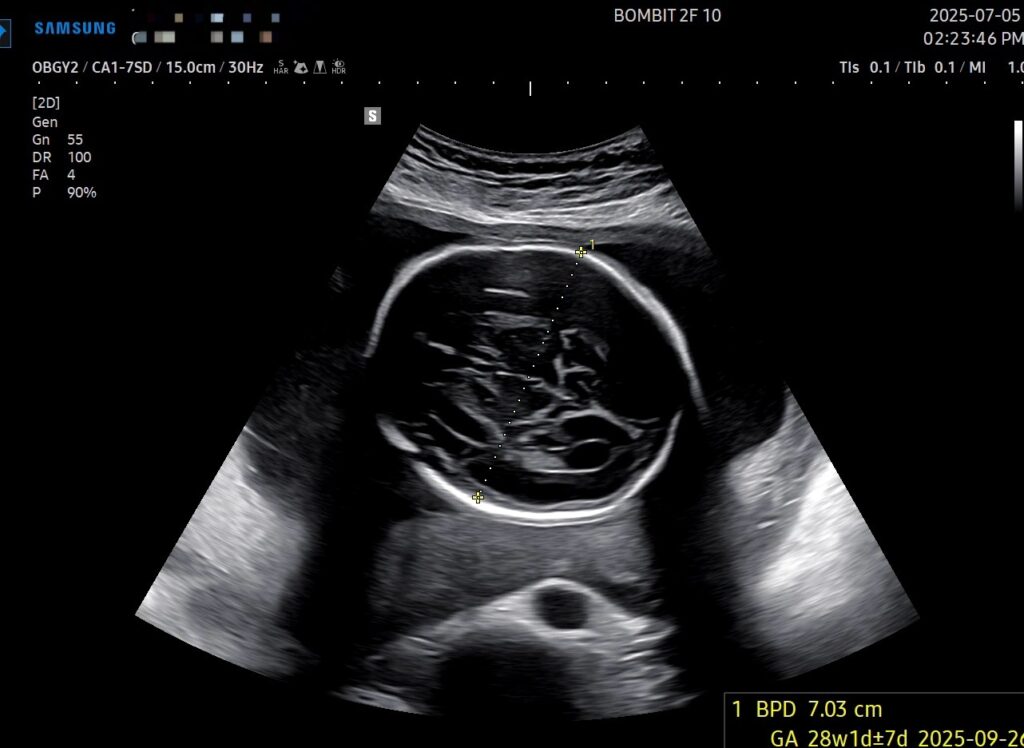

단비는 많이 우량해졌다.

주수에 비해 10일~2주 정도 더 크다고 한다. 초음파 본 날 기준, 900g 정도가 표준 무게라는데 단비는 1kg 가 훌쩍 넘어버림..

단비 크기도 큰 데다가 역아라고 해서 조금 걱정이 된다. 그래도 아직은 주수로 26주이고 34주 전까지만 잘 돌면 된다니 일단 그 때까지 지켜봐야 할 것 같다.

이건 초음파 사진!